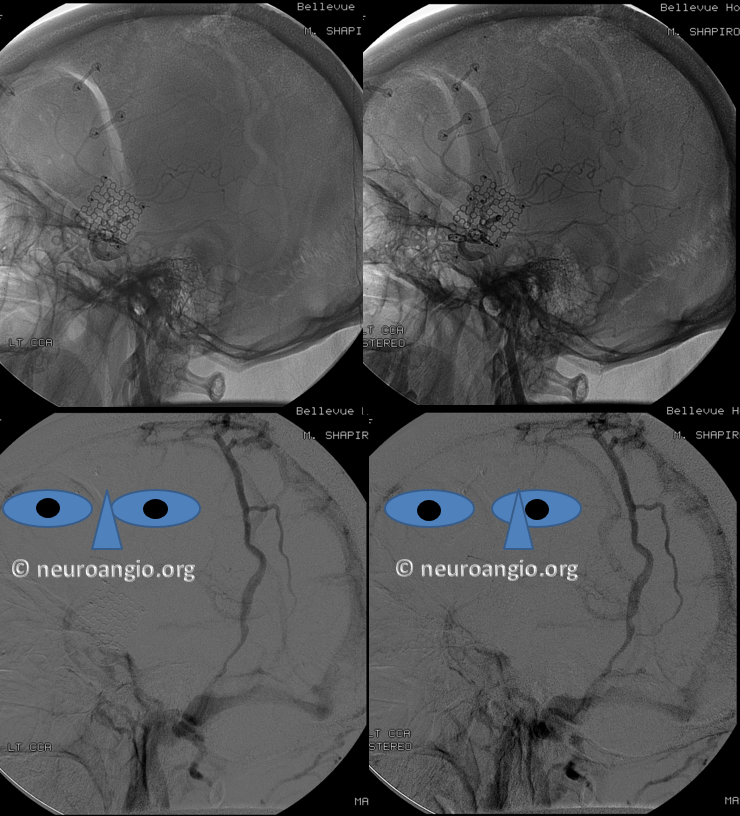

Post venous thrombectomy — with limited results. Note presence of same left diploic vein as seen in right ICA injection, and connection between the distal superior sagittal sinus and the deep venous system via the inferior sagittal sinus.

All of the above anatomic knowledge can become very useful in evaluation of venous thrombosis. Numerous collateral pathways develop in this setting attempting to compensate for the loss. The most dramatic cases usually involve the largest channel — the superior sagittal sinus. In this case, a man presented with what initially was thought to be vasculitis-related brain hemorrhage. Subsequent workup led to an angiogram, where sagittal sinus thrombosis with extensive trans-cerebral and trans-osseous emissary vein collateral channels was seen. In retrospect, these findings were present on the patient’s earlier contrast MRI. “Venovibe” or other contrast-enhanced MR venograms can very sensitive, particularly when interpreted with the appropriate index of suspicion. Noncontrast 2-D time of flight MRV I consider to be next to useless as a problem-solving technique. Any thin-slice postcontrast T1 study is vastly superior.